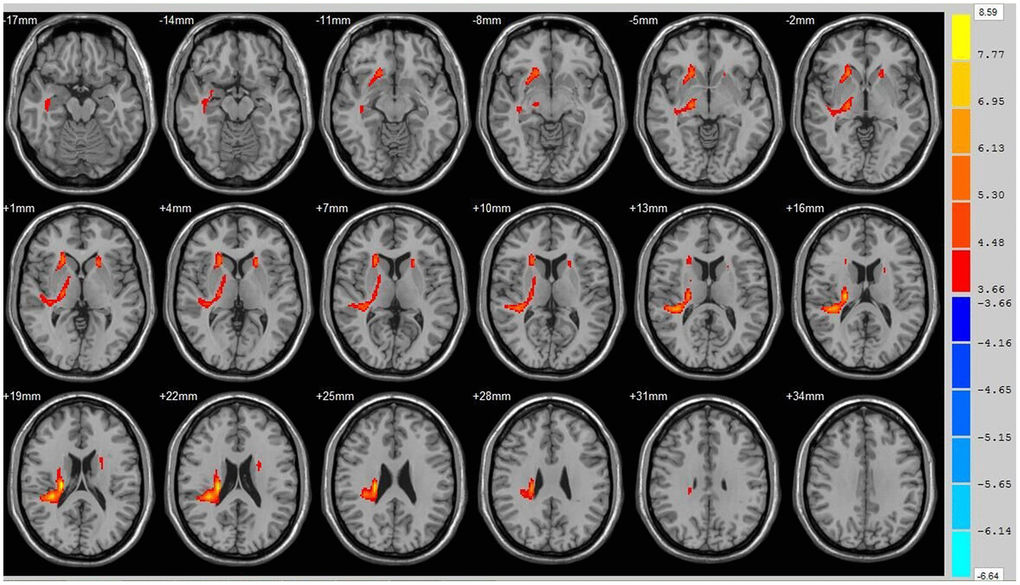

Using the whole brain analysis, we found that 1 week after ICH, patients displayed lower FA values in two brain clusters that included the ipsilateral temporal lobe, frontal lobe, insula, lenticular nucleus, putamen, caudate nucleus, hippocampus and thalamus than did the controls (Figure 1 and Supplementary Table 1). Two clusters with decreased FA values were also observed at week 12 (Figure 2 and Supplementary Table 2). Moreover, 12 weeks after ICH, six clusters (ipsilateral frontal lobe, lenticular nucleus, caudate nucleus, putamen, globus pallidus, and the contralateral parietal lobe, temporal lobe and hippocampus) exhibited higher FA (Figure 3, orange and Supplementary Table 3) while two clusters (ipsilateral limbic lobe, posterior cingulate gyrus and hippocampus) exhibited lower FA than at week 1 (Figure 3, blue and Supplementary Table 4).

Figure 1. Brain areas with decreased FA value at ICH patients at 1st w. Orange means the brain areas which FA value decreased compared with control group at1st w, Threshold=3.6594.